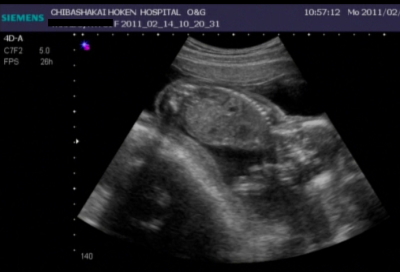

数週間ぶりにエコーで見る赤ちゃんは、少し大きくなっていて右に左に動いたりして、先生が「300円でエコーをDVDに録画できますがしますか?」と言われて「是非!お願いします!」と撮ってもらいました☆

頭が右側で真ん中がお腹らへんです♪

頭の近くの少し黒い影が心臓なのですが、元気に動いていました(*´ェ`*)

今日で19week4dayになります。

以前よりも更に元気に動いていて、性別を聞いたのですが「じっとしてくれないからね~。女の子っぽいけどまだ分からないかな~。」と言われました。